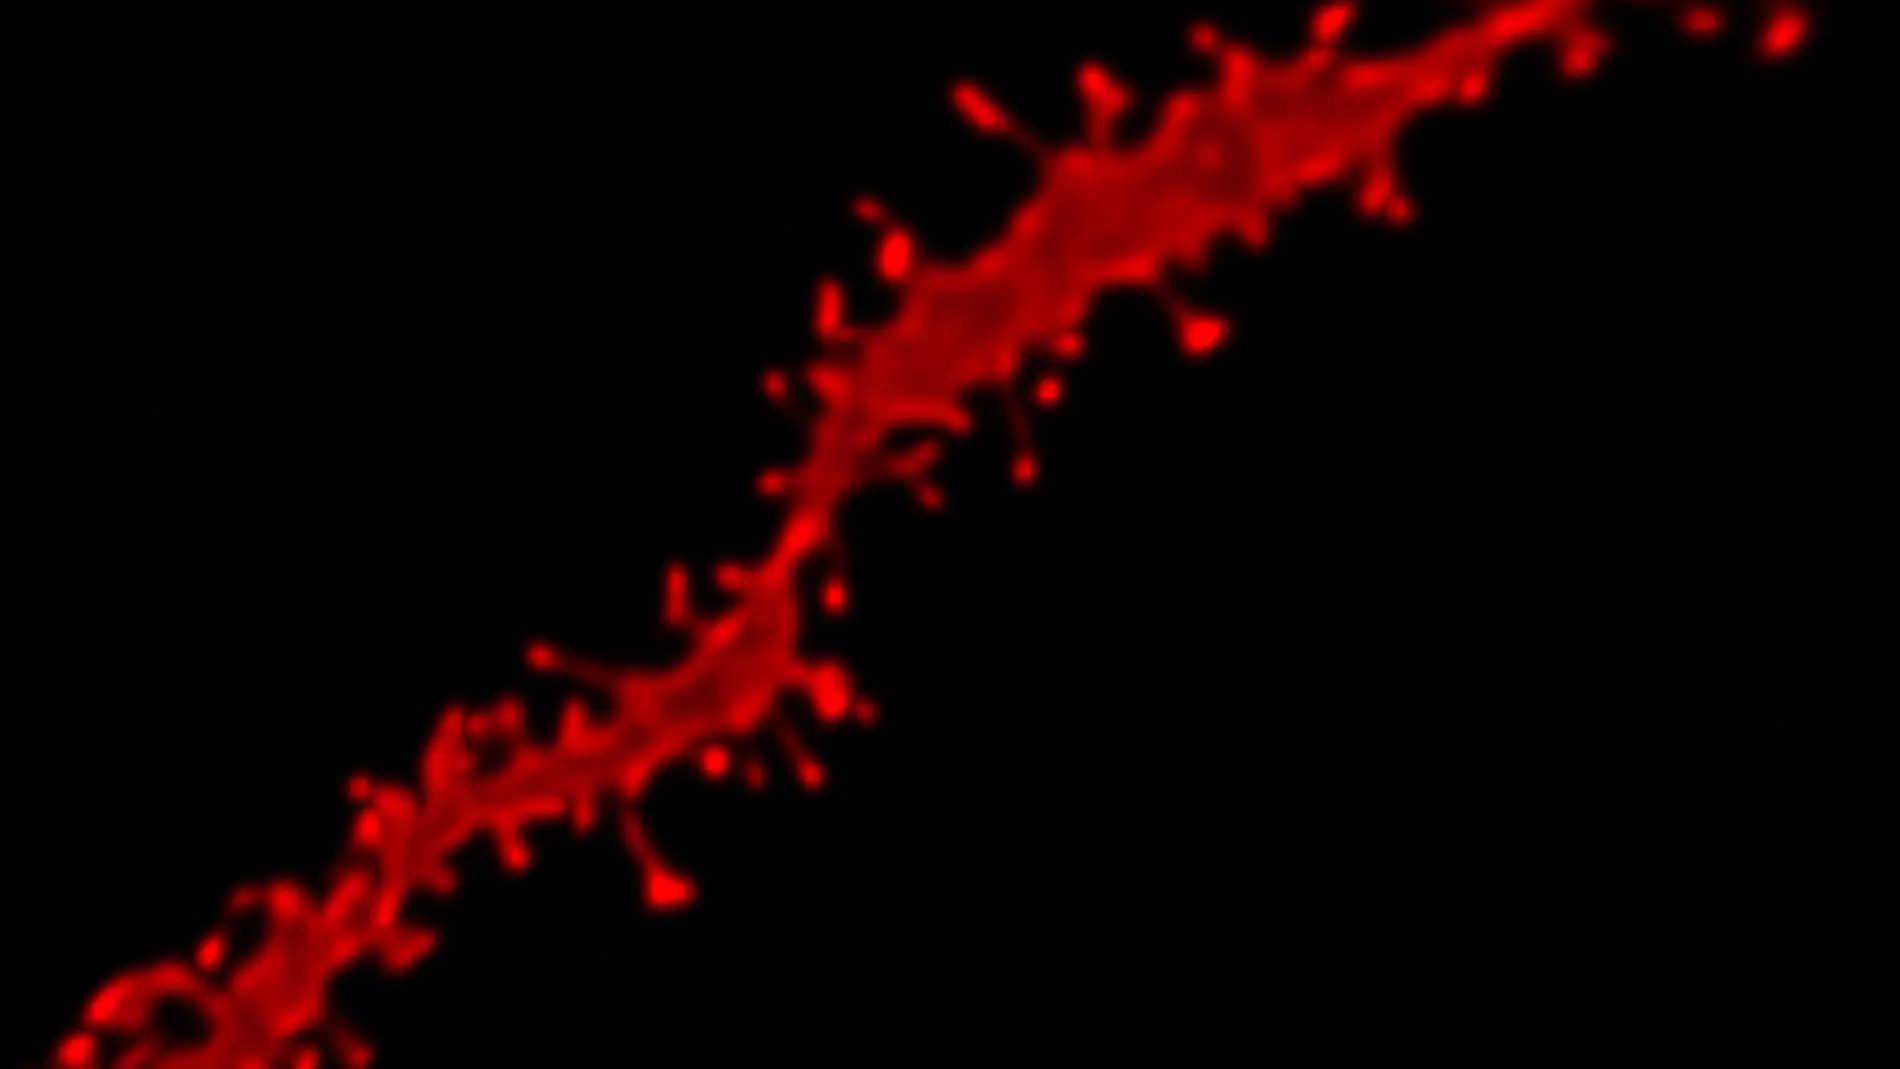

Mediante un análisis morfológico de las neuronas, el equipo investigador ha podido observar un descenso en el número de espinas dendríticas maduras (esto es, las zonas en las que tienen lugar las sinapsis) tras cuatro días sin consumir nicotina. Sin embargo, al eliminar los receptores CB1R situados en una zona concreta del hipocampo, estos cambios estructurales en las neuronas hipocampales, así como los déficits de memoria inducidos por el síndrome de abstinencia a la nicotina no fueron observados.